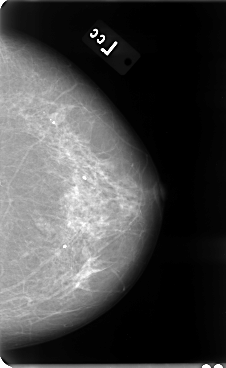

B_3075_1.LEFT_MLO

B_3075_1.LEFT_CC

LEFT_CC LINES 4776 PIXELS_PER_LINE 2936 BITS_PER_PIXEL 12 RESOLUTION 50 NON_OVERLAY

LEFT_MLO LINES 4760 PIXELS_PER_LINE 2792 BITS_PER_PIXEL 12 RESOLUTION 50 NON_OVERLAY